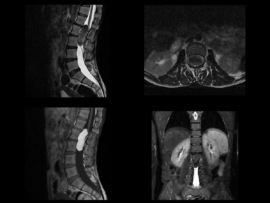

45 YEAR OLD MALE, Presenting compaints: Patient presented with lower back pain since 5 years; right leg numbness and tingling since 6 months and acute onset urinary incontinence